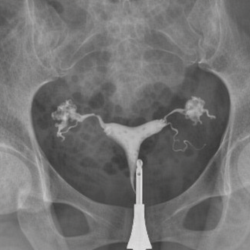

Yumurtalık kistleri, kadınlarda oldukça sık görülen ve çoğu zaman iyi huylu olan oluşumlardır. Çoğu kist herhangi bir belirti vermez ve kendiliğinden kaybolabilir. Ancak bazı durumlarda kistler büyüyebilir, ağrıya neden olabilir, adet düzensizliklerine yol açabilir veya nadiren ciddi komplikasyonlara neden olabilir. Özellikle büyük boyutlara ulaşan, hızlı büyüyen ya da şüpheli görünüme sahip kistlerin cerrahi olarak çıkarılması gerekebilir.

Kistin türüne göre tedavi yaklaşımı değişebilir. Fonksiyonel kistler, endometrioma (çikolata kisti), dermoid kistler veya diğer kompleks kistler farklı şekillerde değerlendirilir ve her biri için uygun tedavi planı oluşturulur. Bazı kistlerin çıkarılması, hem ağrı şikayetlerini azaltır hem de gebelik şansını olumlu yönde etkileyebilir.